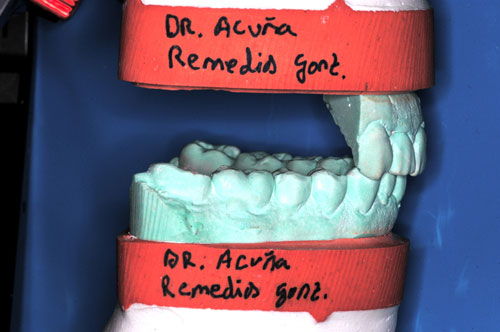

ESTUDIO ESTÁTICO DE LOS MODELOS PREVIOS A LA PRIMERA REHABILITACIÓN APORTADOS POR LA ENFERMA:Modelos Color Blanco

B- ESTUDIO ESTÁTICO DE LOS MODELOS PREVIOS A LA 1ª REHABILITACIÓN APORTADOS POR LA ENFERMA: (La situación oclusal que la enferma tenía antes de que la tocara un dentista (MODELOS COLOR BLANCO)

Diferencias entre ambos modelos:

A nivel de segundos molares= 4 mm +

A nivel de primeros molares= 3,50 mm +

A nivel de incisivo central=5,50 mm +